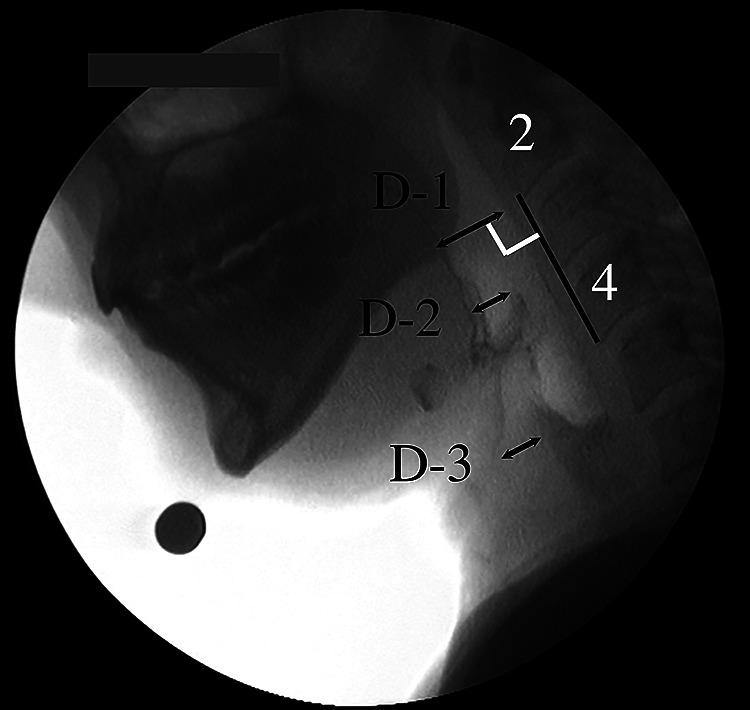

Ten healthy volunteers participated in the study. The head and neck were set in neutral (N), head flexion (HF), neck flexion (NF) or combined head-and-neck flexion (HFNF) positions. Participants were instructed to swallow 4 ml of thick barium liquid in an upright sitting position. Head and neck angles at rest, distances in the pharynx and larynx at rest, and duration of swallowing were measured. Statistical analysis was performed with a paired t-test with Bonferroni correction.

Head angles in HF, NF and HFNF positions were significantly greater than in the N position. Neck angles were significantly greater in the NF position than in the N position. The distance between the tongue base and the posterior pharyngeal wall, the vallecular space and the airway entrance were smaller in the HF position than in the N position. The tongue base was in contact with the posterior pharyngeal wall longer in the HF position than in the N position.